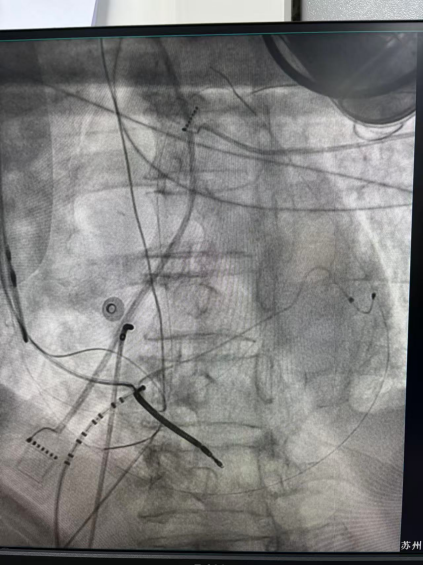

心外膜基质

王林林主任医师谨慎操作,成功进入心外膜达到病变位置。术中,患者反复自发多形态室速,且转为室扑,同时出现血流动力学不稳定,需多次电除颤方能终止发作,标测难度极大。这就要求医疗团队必须在有限的标测时间内精准定位室速消融靶点,并结合心内外膜基质特征制定消融策略。经针对性消融后,患者未再自发室速,且室性早搏转为单一形态,经判定为右心室乳头肌来源,随即予以一并消融。术后经心室程序电刺激验证,室速未再被诱发。